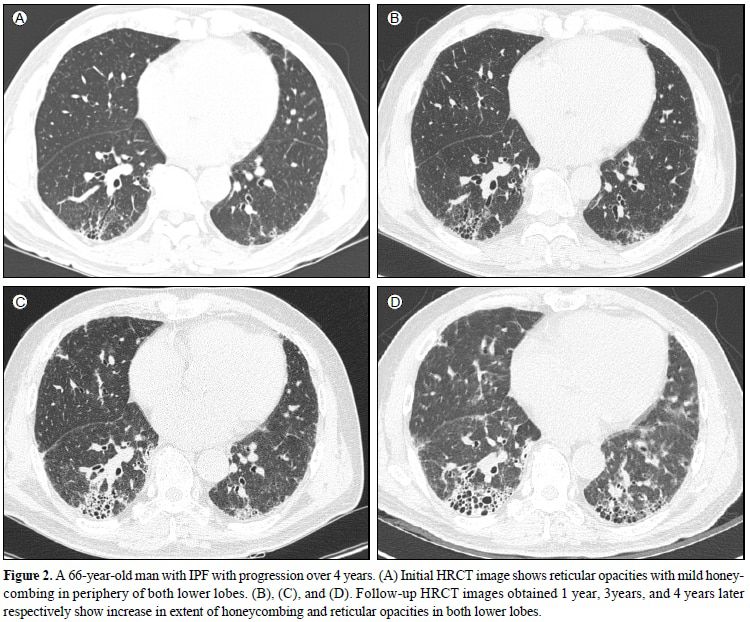

66세 특발성 폐섬유증 환자의 흉부방사선사진. 왼쪽 위(1년)부터 오른쪽 아래(4년)까지 병의 진행 상황을 볼 수 있다. 양측 폐에서 섬유화된 면적이 넓어지면서 병이 깊어진다. /고려대 안암병원 영상의학과 제공